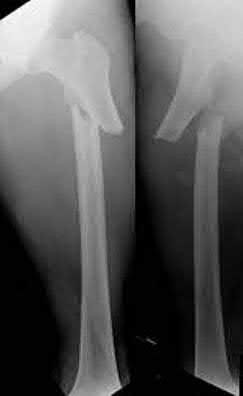

A 12-year-old boy presents with left thigh pain, an antalgic gait, and an externally rotated left lower extremity. Radiographs demonstrate the pathology shown. Which of the following is considered an absolute indication for prophylactic pinning of the asymptomatic, contralateral hip in a patient presenting with Slipped Capital Femoral Epiphysis (SCFE)?

SCFE is characterized by a displacement of the proximal femoral epiphysis. Prophylactic pinning of the contralateral hip is somewhat controversial but generally recommended in patients with a high risk of subsequent contralateral slip. Absolute indications or highly strong recommendations for prophylactic contralateral pinning include an underlying endocrine disorder (such as hypothyroidism or growth hormone deficiency), renal osteodystrophy, previous radiation therapy, and presentation at a very young age (e.g., < 10 years). Endocrine disorders dramatically increase the risk of bilateral involvement, often occurring simultaneously or sequentially.